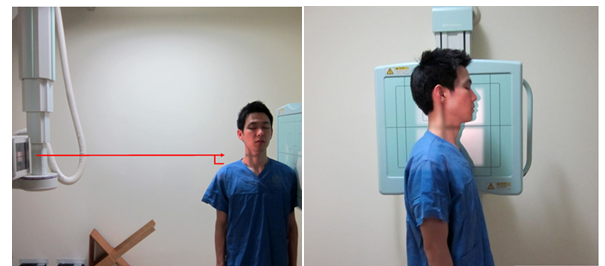

C-Spine Lateral

1) 환자자세

① 환자를 true lateral로 세우고 턱을 약간 들고 어깨의 힘을 빼도록 한다.

② C4 (adam’s apple)를 향해 수직 입사한다.

2) 호흡법 : 움직임이 없도록 숨을 멈춘 후 검사한다

5) 촬영 거리 : SID는 180cm으로 촬영한다.